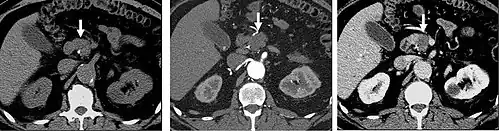

FIGURE 1. Non-contrast CT demonstrating multiple bilateral renal calculi (arrows), which can be obscured on contrast-enhanced images, particularly delayed images when there is excreted contrast in the renal collecting system; axial left, coronal reformat on right.

Non-contrast CT scans Figure 1a (left) and 1b (right) are of limited use for the differentiation of soft tissue structures. However, materials like blood, calcium (renal stones, vascular atherosclerosis), bone, and pulmonary parenchyma are highly visible and can usually be adequately assessed with non-contrast CT. For example, in the abdomen and pelvis, there are several indications for non-contrast imaging. These include: evaluation of renal calculi; assessment for gross intra-abdominal hemorrhage; and post-endostent volume measurements. In addition, non-contrast images are often obtained in conjunction with contrast enhanced images in evaluating potential renal transplant donors and in the evaluation of the pancreas (in combination with contrast phases). Of note, dual-energy CT and the development of virtual "non-contrast" images (VNC imaging) may ultimately obviate the combination scans. Additionally, CT angiography examinations performed for pathologies like aneurysms and dissection are frequently performed in conjunction with non-contrast imaging. The non-contrast images facilitate the differentiation of active extravasation or acute bleeding from vascular calcifications.